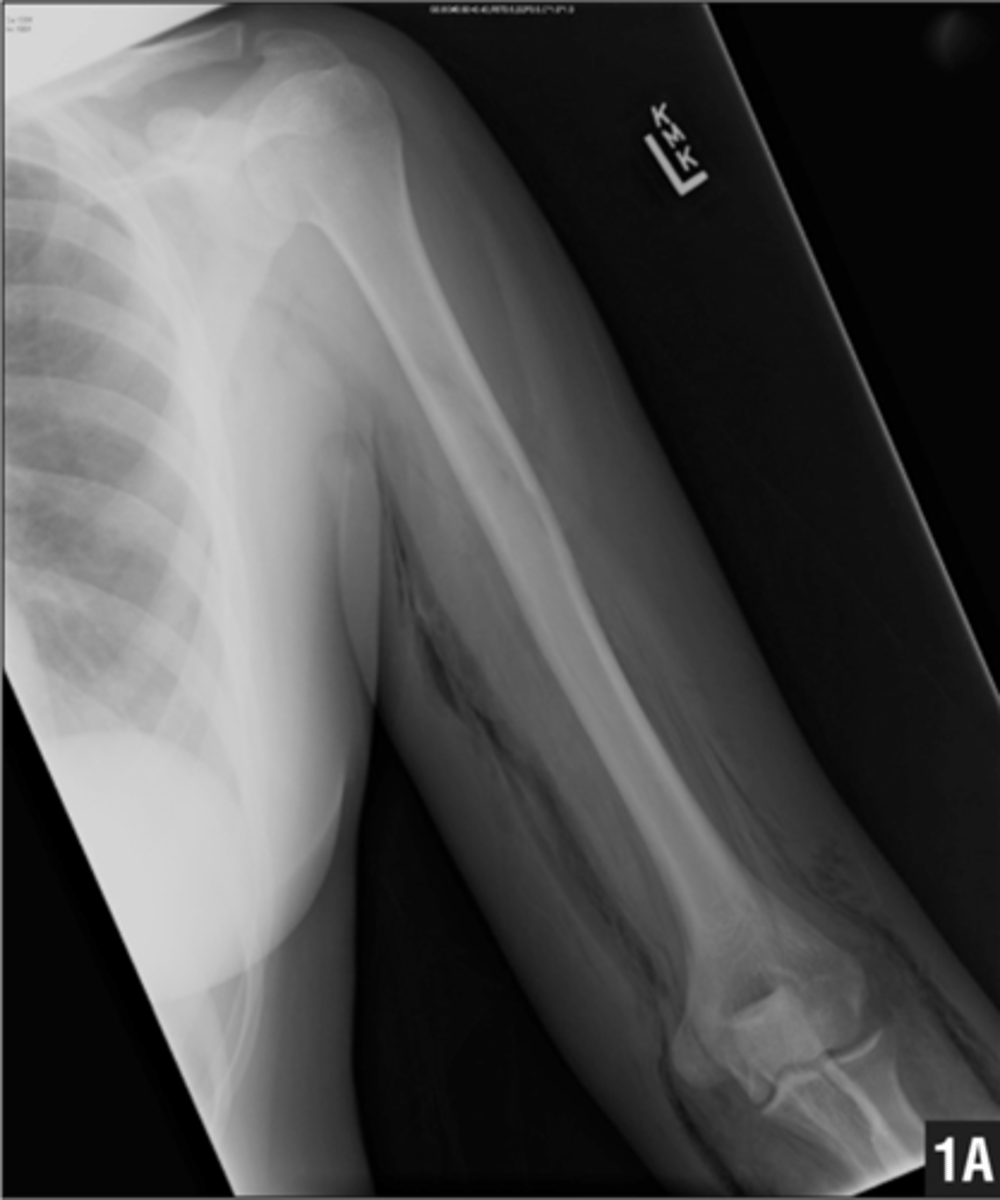

Where do you measure for extremities radiograph?

point of pain in the center.